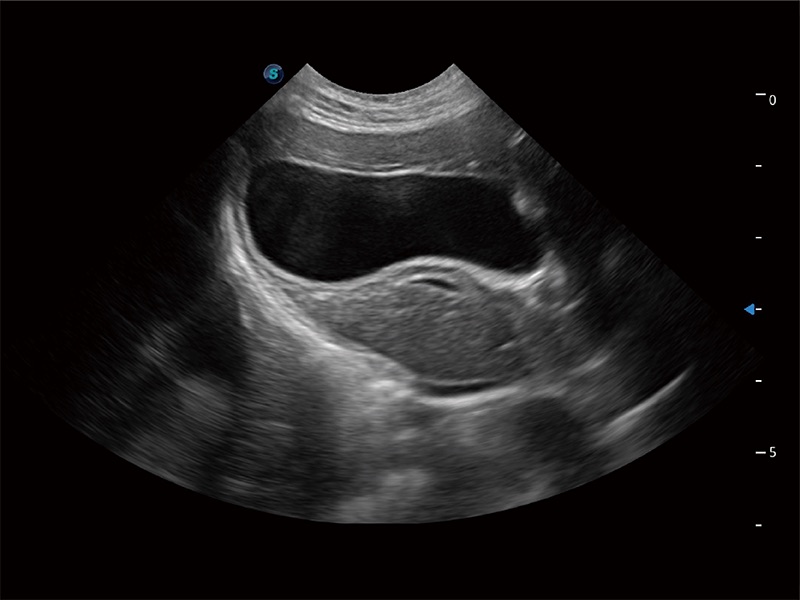

优异的基础图像

ProPet 80 全新的动物超声智能软件和丰富的探头群,为动物医生提供了高清晰度和精细分辨率的图像,无论在宠物、马科、畜牧还是实验室动物等应用中都可以轻松应对,为您的日常工作带来满意的体验。

(犬)肝脏

(猫)胆囊

• Auto Bladder 膀胱自动测量

一键自动识别膀胱壁及自动测量膀胱容积,不受膀胱形状和大小的限制,帮助医生快速精准获得测量的数据。